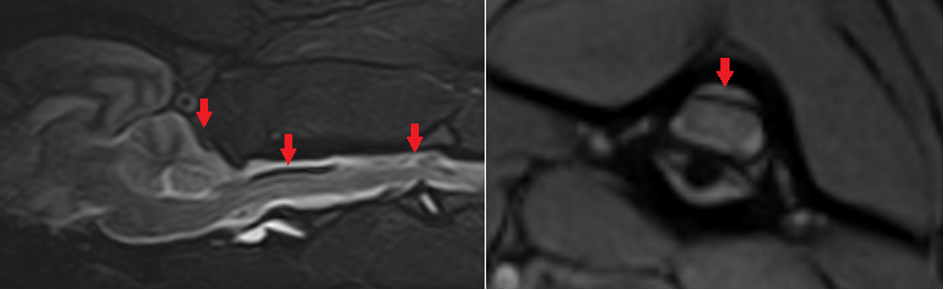

Na overleg met de eigenaren werd gekozen voor een MRI-scan van de kop en nek (waarvoor Kwibus ook verwezen was). Daarop werden diverse afwijkingen gezien, waaronder heterogeniteit van de subarachnoïdale ruimte (waar de cerebrospinale vloeistof stroomt), met hyperintensiteit op pre-contrast T1‑gewogen beelden en signal void op T2* (indicatief voor bloedproducten zoals hemoglobine) (Figuur 1). Deze afwijkingen waren verspreid vanaf de caudale craniale fossa (achterhoofd) tot de derde thoracale wervel.

Een subarachnoidale bloeding werd gediagnosticeerd op basis van deze bevindingen. SRMA kan gepaard gaan met bloedingen in of net buiten het ruggenmerg of de hersenen, maar er zijn ook andere oorzaken voor deze bloedingen mogelijk. Een belangrijke differentiaaldiagnose is een hemorragische diathese om wat voor reden dan ook. Als meest voorkomende oorzaak daarvan wordt bij neurologische patiënten een infectie met Angiostrongylus vasorum gerapporteerd. Vanwege het risico op aanvullende bloedingen werd gekozen geen liquorpunctie uit te voeren.

De combinatie van MRI-bevindingen (T1-hyperintensiteit, T2*‑signal void, meningeale contrastversterking) bleek belangrijk voor het stellen van de diagnose. De casus toont het belang van een betrouwbare diagnose van Angiostrongylus-infecties, waarbij Baermann-methode cruciaal kan zijn, zeker bij een negatieve antigeentest. Ernstigere neurologische afwijkingen zoals door hersenbloedingen zijn voorkomen door tijdige behandeling.